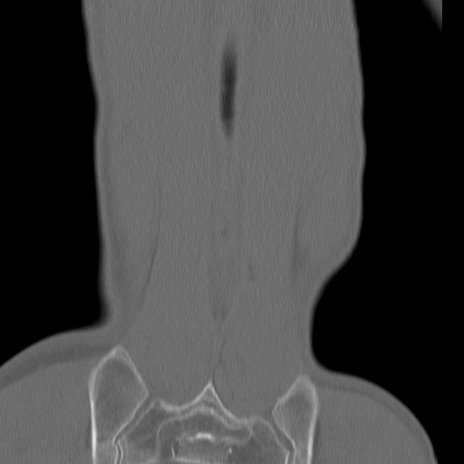

症例3 腰椎CT(冠状断像)

腰椎CT

3D再構成